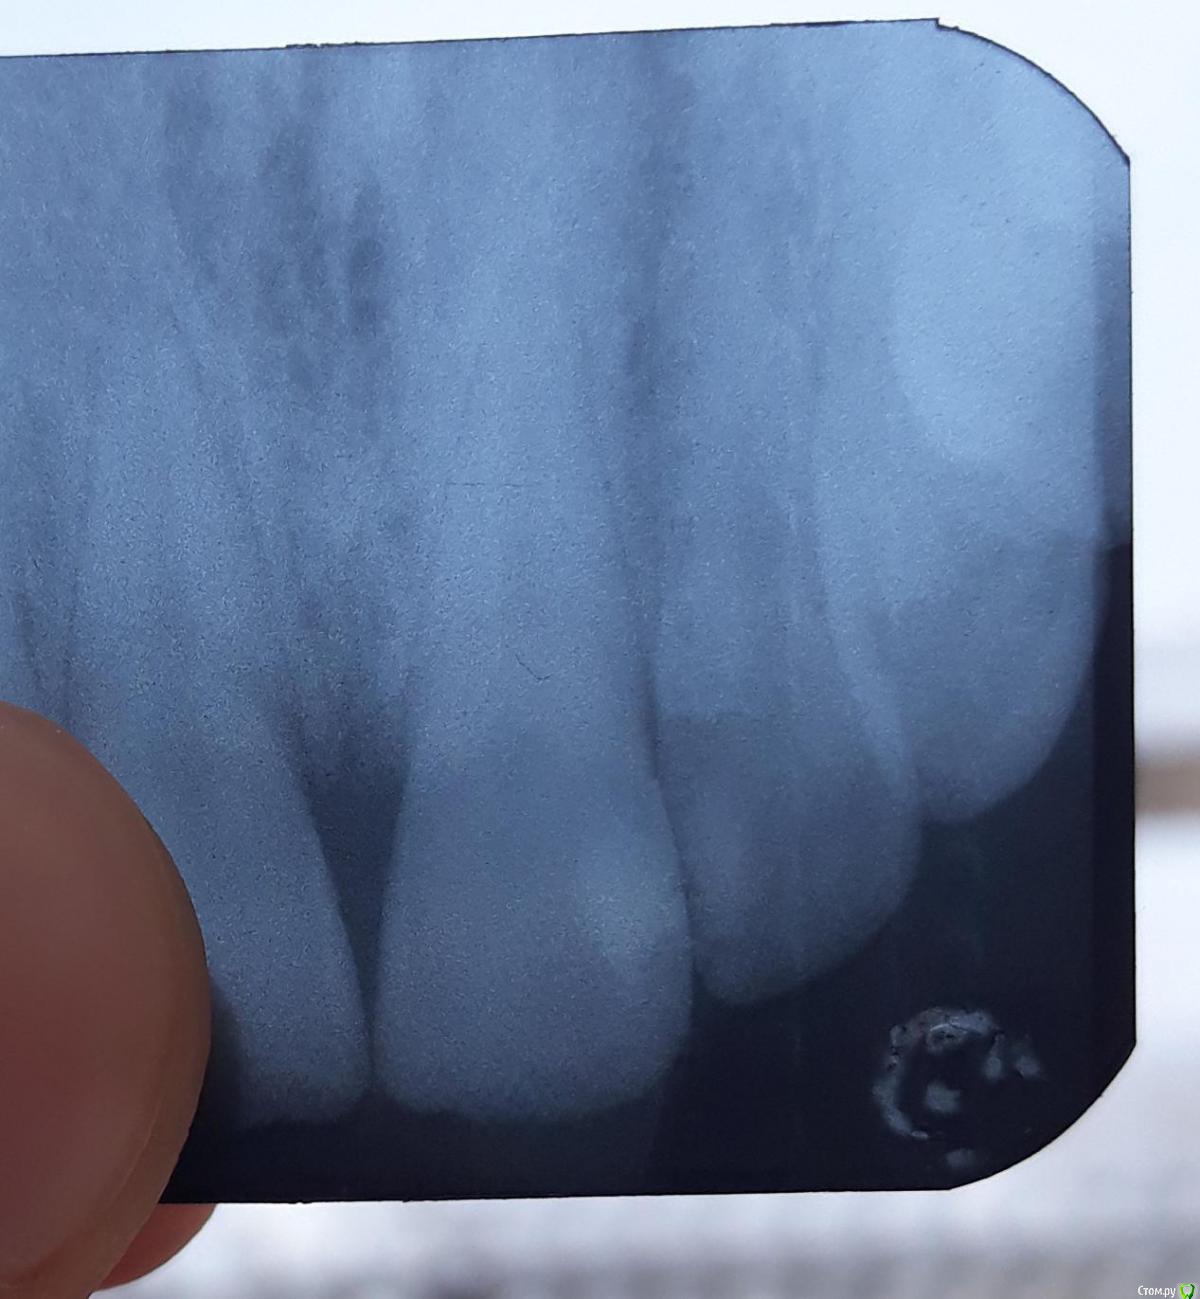

ВиталийВиталий Опубликовано 24 января, 2019 Поделиться Опубликовано 24 января, 2019 (изменено) Здравствуйте! Прошу Вас дать рекомендации. как поступить в моем случае? Менее недели назад лечил передние зубы, ставились светоотверждаемые пломбы. Сзади зуба с трещиной так же массивная пломба. Пломба, кстати, не шатается. Трещина распостранилась на зону удаления кариеса (граница трещины-граница пломбы сзади). Зуб не болит, чувствительность присутствует, но не сверхъестественная. и то лишь на длительное воздействие холодного воздуха. Под десну трещина не заходит. Повторюсь что сзади трещины пломба. Зуб с нервом.Как можно "заделать" трещину и предотвратить ее разрастание? Вопрос обусловлен тем, что в наших стоматологиях увы любят навязывать прочие услуги, которые в ряде случаев не являются необходимыми. Изменено 24 января, 2019 пользователем ВиталийВиталий Ссылка на комментарий

red_butler Опубликовано 24 января, 2019 Поделиться Опубликовано 24 января, 2019 покажите Rg зуба Ссылка на комментарий

ВиталийВиталий Опубликовано 24 января, 2019 Автор Поделиться Опубликовано 24 января, 2019 покажите Rg зубана снимке не видно трещины, поэтому не стал прикреплять. Ссылка на комментарий

red_butler Опубликовано 24 января, 2019 Поделиться Опубликовано 24 января, 2019 на снимке не видно трещины, поэтому не стал прикреплять. Я хочу посмотреть объем реставрации Ссылка на комментарий

ВиталийВиталий Опубликовано 24 января, 2019 Автор Поделиться Опубликовано 24 января, 2019 Я хочу посмотреть объем реставрацииПрикрепил в описание темы) Ссылка на комментарий

red_butler Опубликовано 24 января, 2019 Поделиться Опубликовано 24 января, 2019 Ничего страшного нет, делать ничего не нужно 1 Ссылка на комментарий